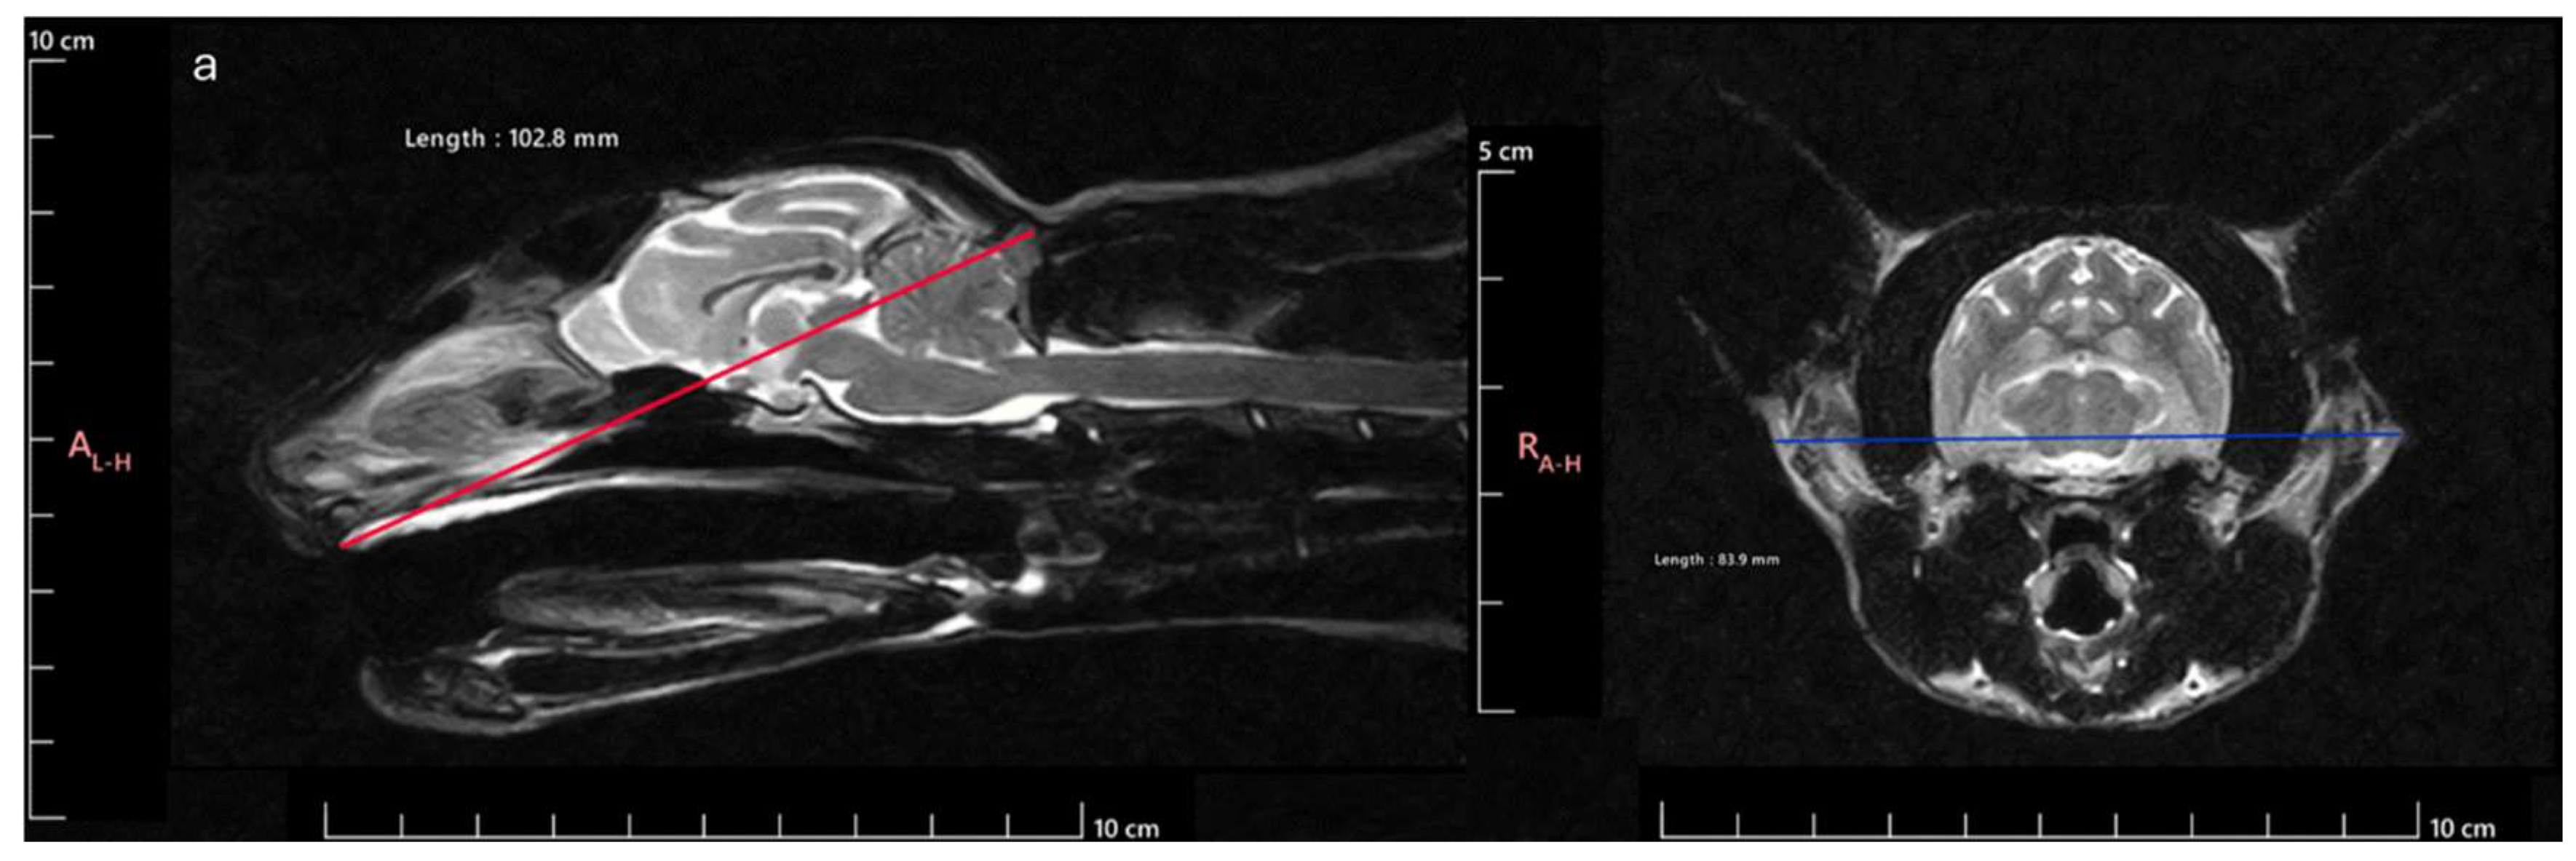

Figure 1. Cranial measurements necessary to determine the SI: a) SL measurement: distance between the inion and the prosthion; b) SW measurement: distance between the outer margins of the zygomatic arches.